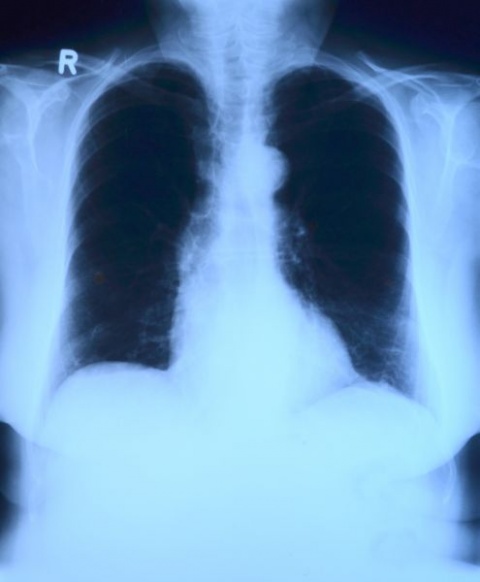

El servicio de emergencias de Francia está al frente de la crisis del coronavirus. (Fuente: Centre hospitalier d’Argenteuil)